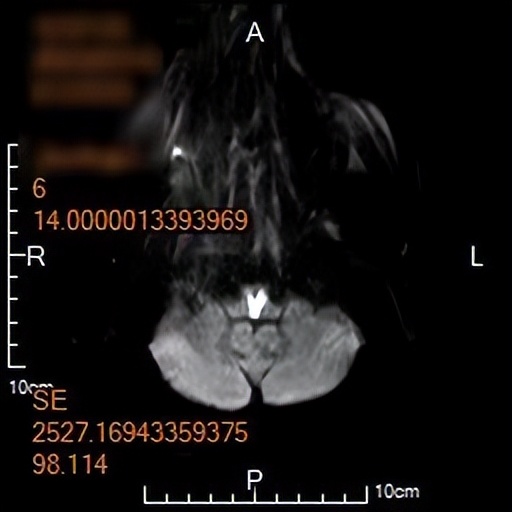

神经内五科医生接诊后完善相关检查,经评估后考虑是脑卒中(俗称中风)。在进一步的头颅磁共振检查中,图像上赫然出现的“心形图案”,印证了最初的猜测,这是脑梗死中罕见的“心形梗死”——双侧延髓内侧梗死(BMMI)。